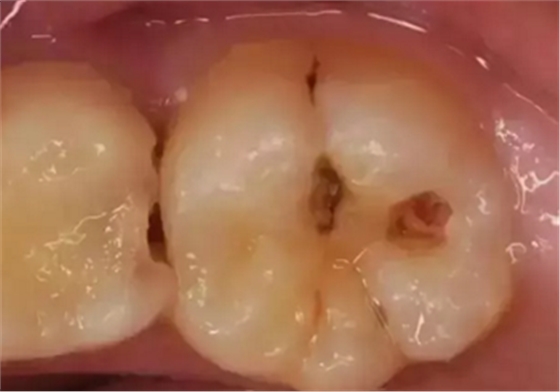

蛀牙從外表看就表現(xiàn)為一個(gè)黑點(diǎn),通常位于窩溝點(diǎn)隙(牙面上點(diǎn)狀或線狀凹陷)

淺齲——侵犯牙釉質(zhì):起初的蛀牙只限于牙齒表面淺層,牙面上會(huì)出現(xiàn)一個(gè)小黑點(diǎn),不痛不癢,所以很容易被我們忽視。

中齲——感染牙本質(zhì)表層:到這個(gè)階段,已經(jīng)能看到明顯的蛀洞,此時(shí)的病變位于牙本質(zhì)的淺層,牙齒會(huì)冷熱酸甜敏感,但是離開刺激物就沒有不適感。

深齲——滲透牙本質(zhì)深層接近牙髓:此時(shí)的病變已經(jīng)發(fā)展到牙本質(zhì)深層接近牙髓了,有明顯的蛀洞且較深,伴隨明顯的牙痛,遇到外界刺激痛感加重,牙齒變得很敏感,還會(huì)出現(xiàn)食物鑲嵌在牙洞的情況。